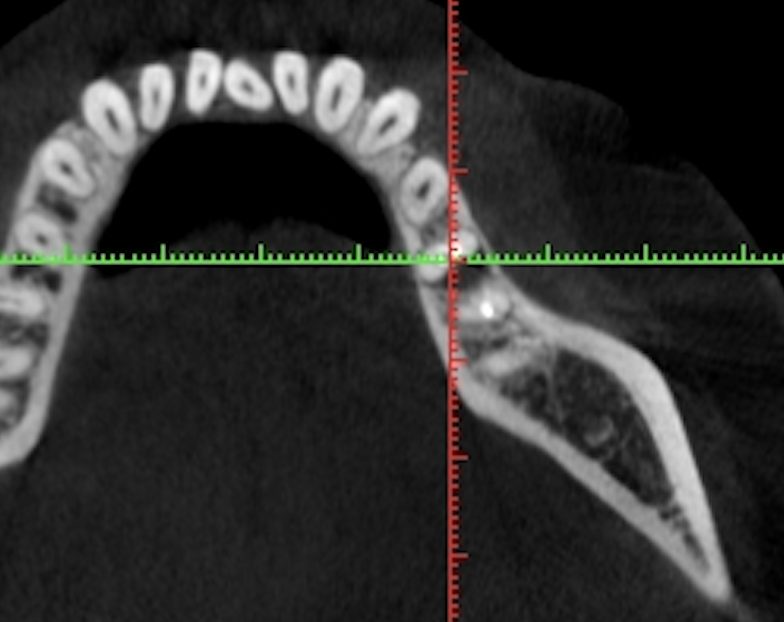

◎歯科用CT画像とレントゲン写真の違いは?

写真は同一部位のレントゲン写真とCT画像です。レントゲン写真は顎骨の形態や走行する神経の位置、歯が生えている方向把握することはできても2次元的な位置関係でしか把握できません。つまり歯や神経の位置がわかっていても実際にどのくらいの位置関係にあるのかを正確に判断することはレントゲン写真では不可能なわけです。しかし、歯科用CT画像では顎骨の形態や走行する神経の位置、歯の生えている方向、さらには骨密度の状態を3次元的に画像化する事が可能なため、より正確な診断する事ができます。